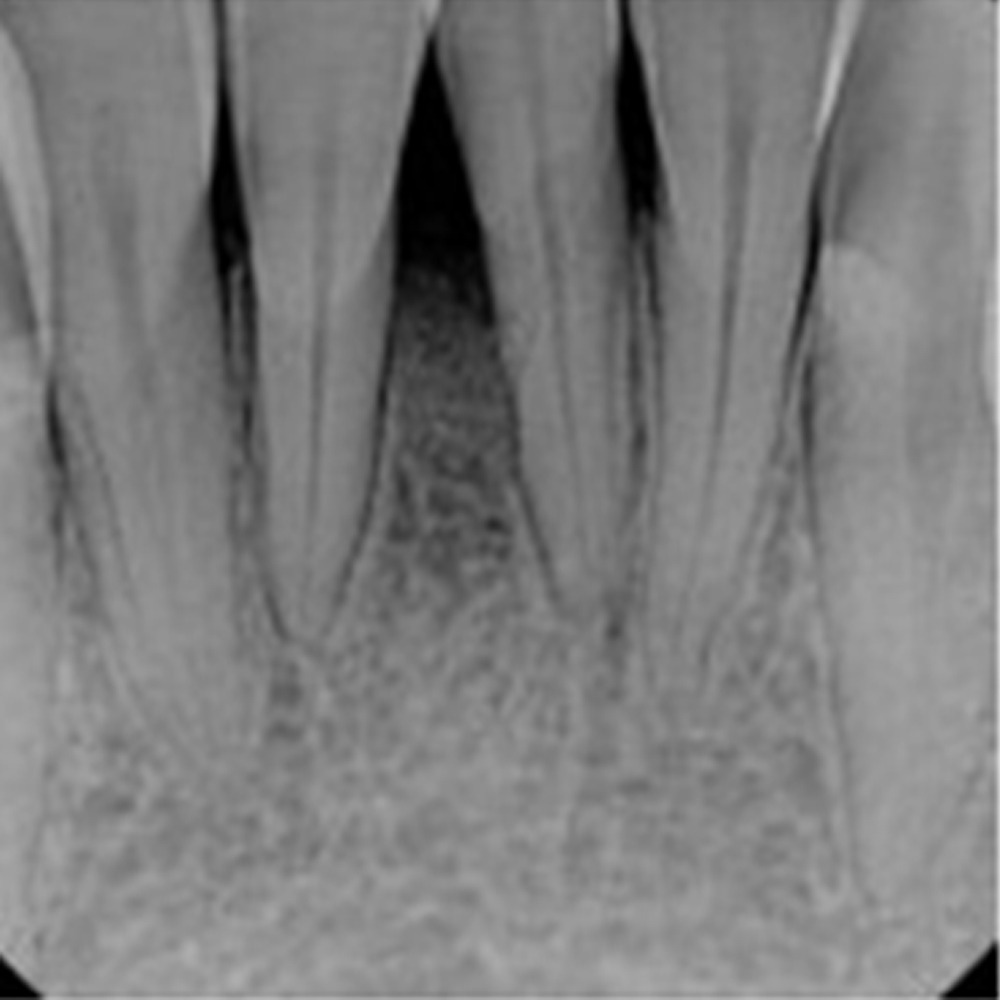

However, in some situations, there is not enough bone tissue, so the bone tissue is strengthened by bone powder.But you may ask, why does the bone degenerate? Bone loss is possible in many conditions and problems. However, the main reason for jaw bone loss is tooth loss.

When a tooth is lost, the jaw bone in that area will degenerate over time. If this bone loss is too severe, bone grafting is necessary.